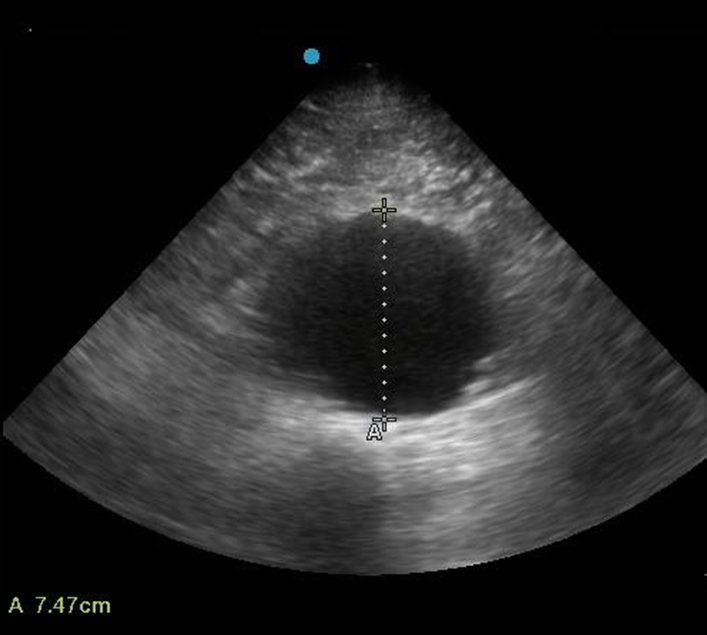

1) US

(1) AAA의 지름 측정: Serial screening으로 적합

(2) 혈전도 발견 가능하며, 대신 파열은 찾기 어려움